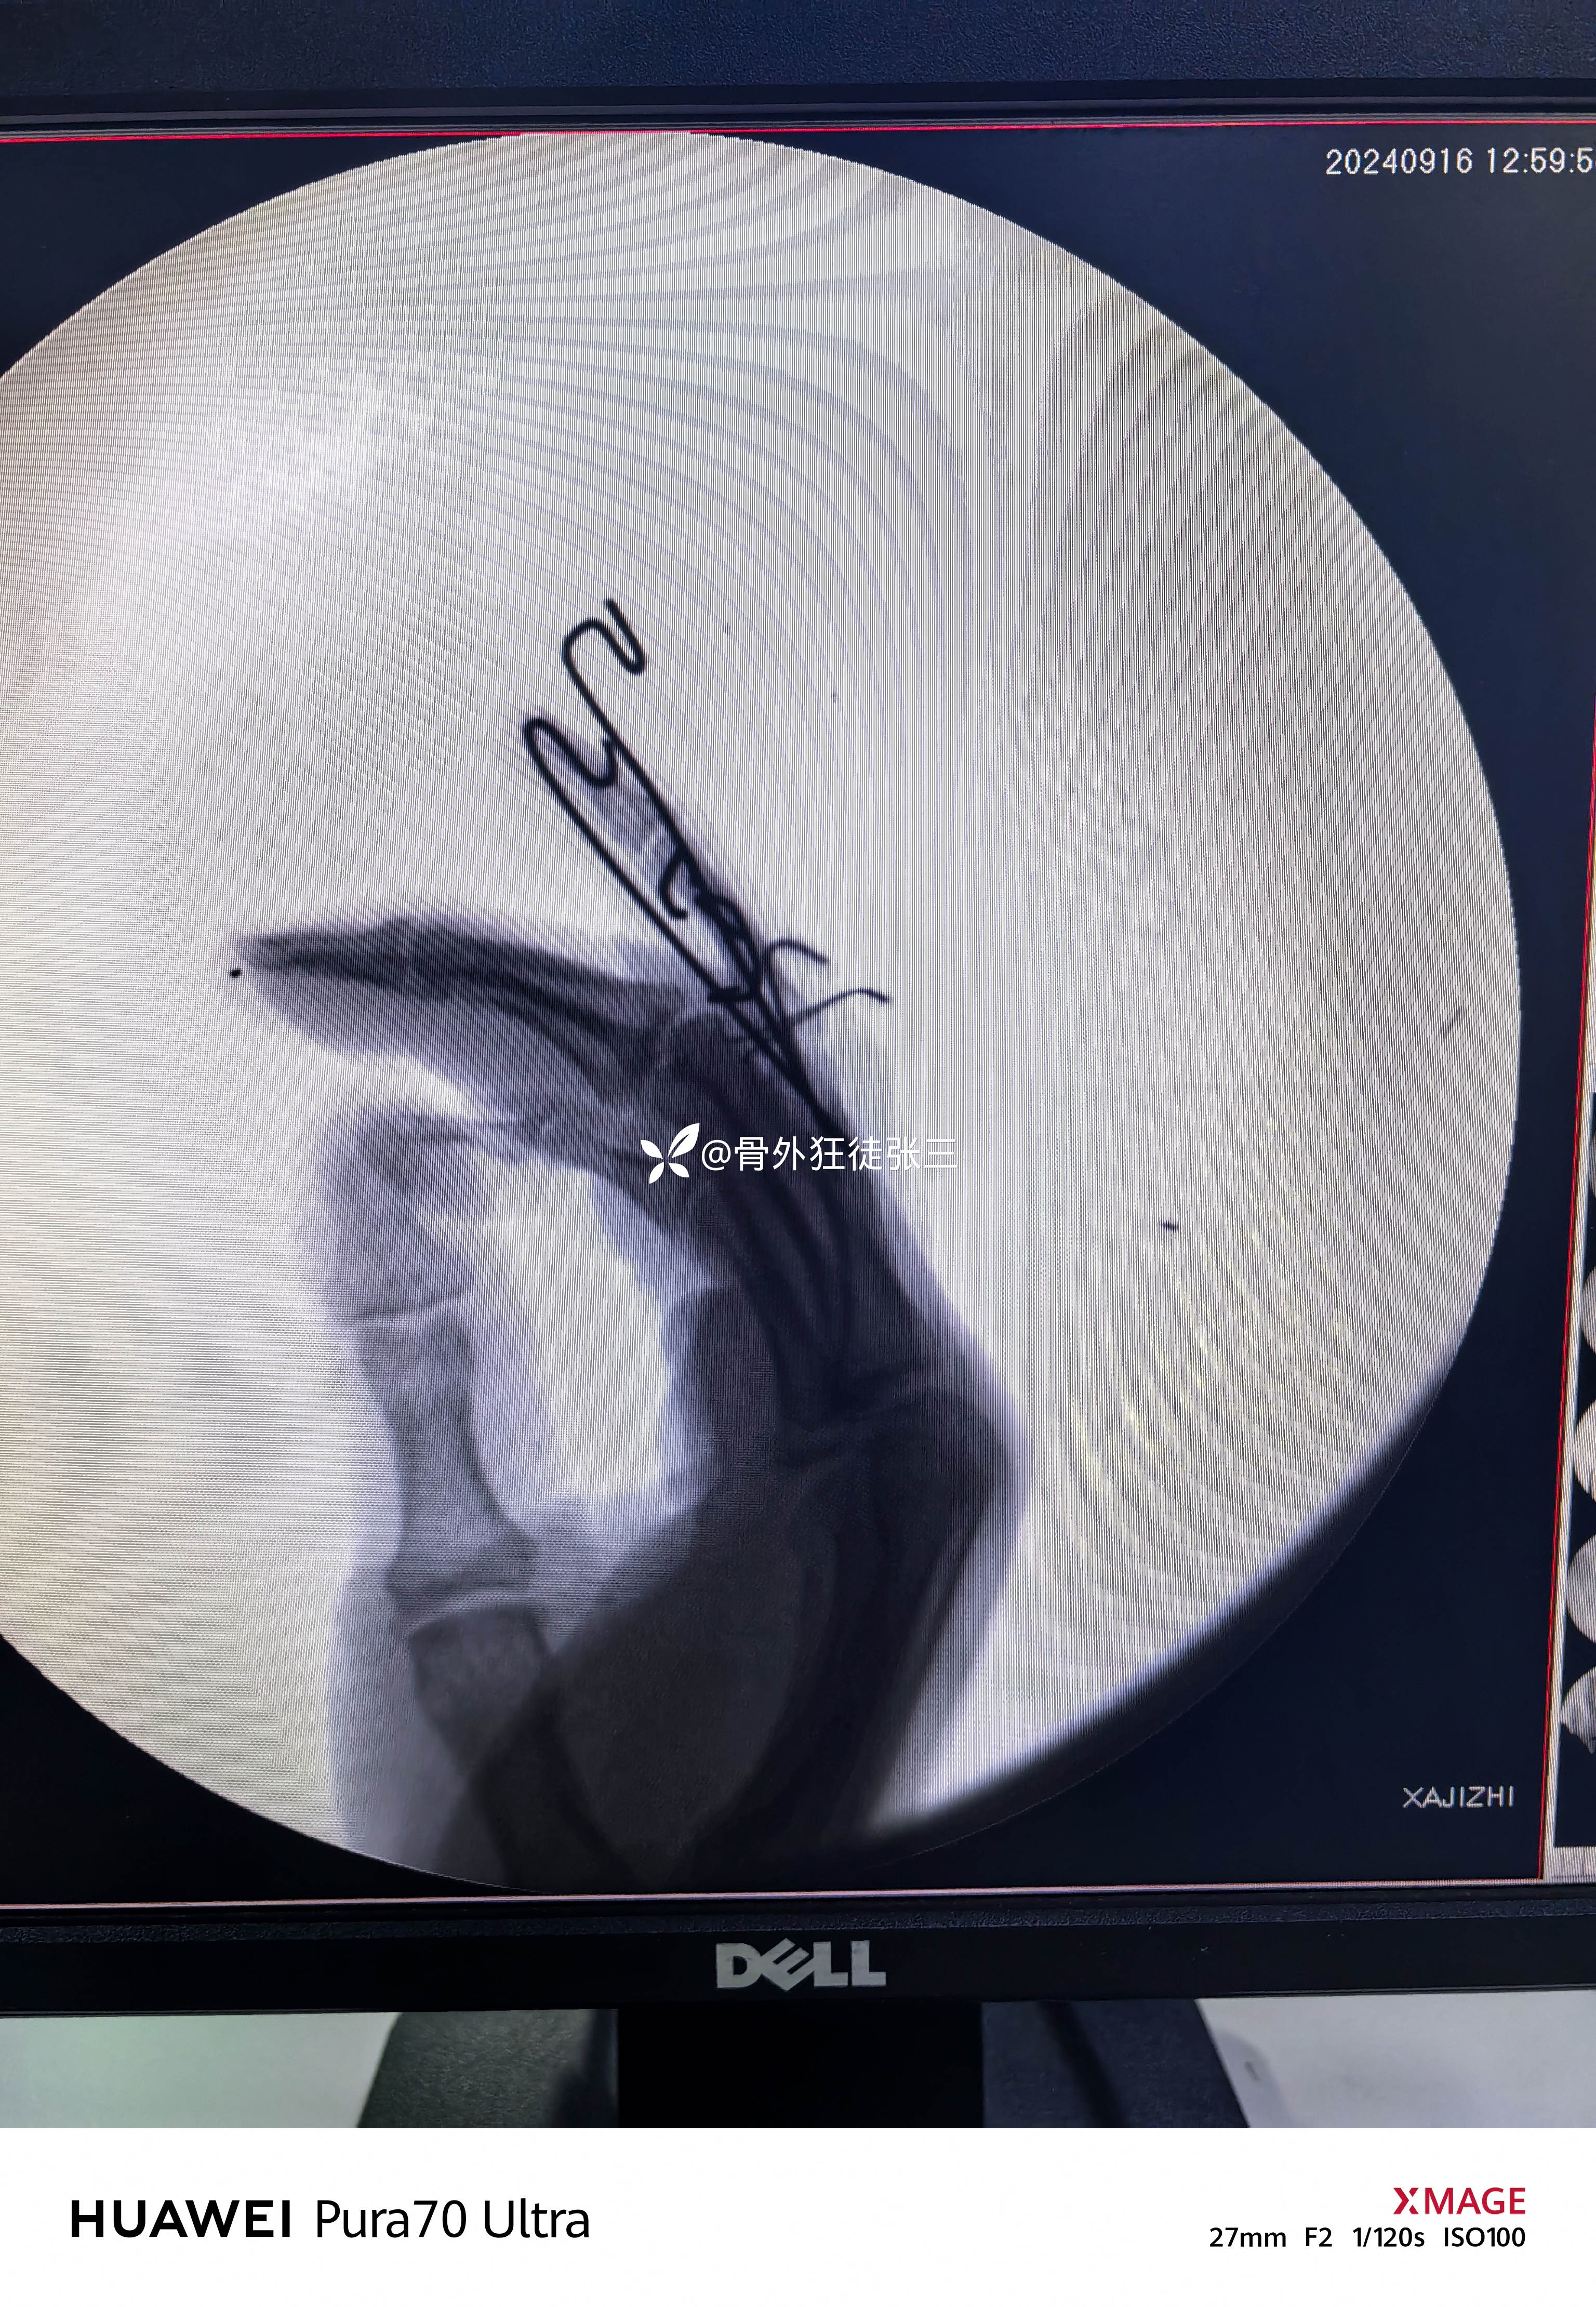

四,临床实战

先穿针

“针人针事”

一分钟一根针

折弯,橡皮条牵引

透视发现,无法纠正脱位和骨折

从掌侧in-out-in穿出

折弯阻挡骨块

透视发现骨块无法复位

脱位无法纠正

于是乎

先复位脱位,再透视

发现关节不稳无法维持复位

只能克氏针固定关节

保持复位

再次用阻挡克氏针复位骨块

透视发现骨块复位

关节复位